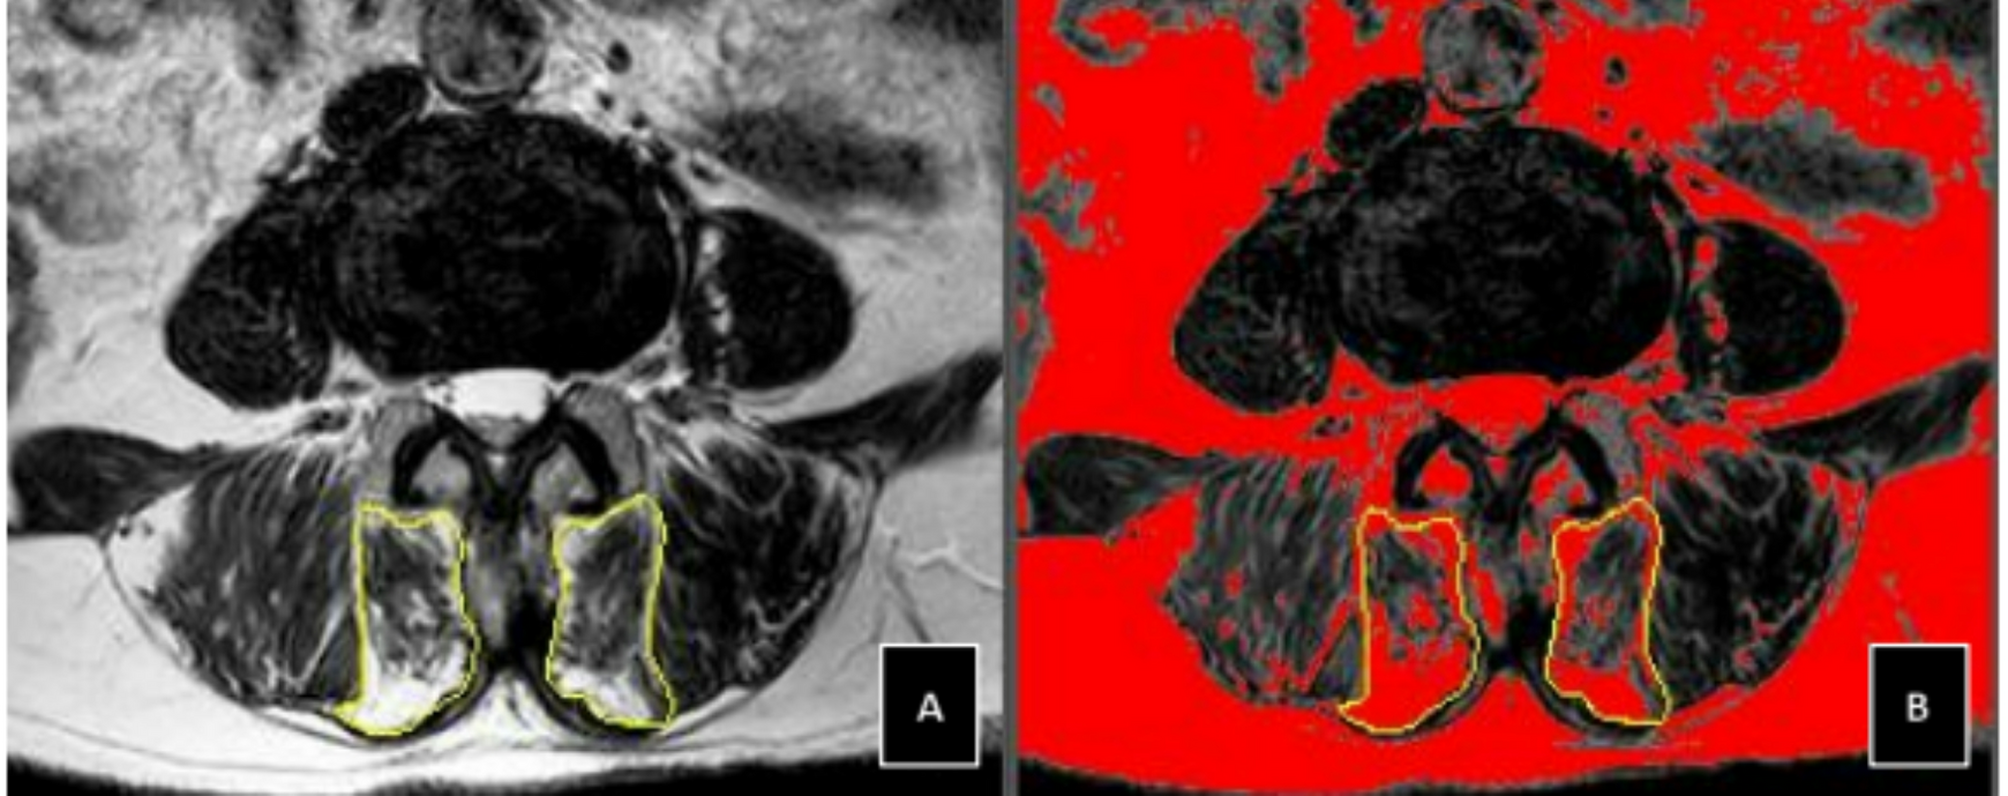

Fig. 3

Measurement of LCSA/GCSA on axial T2-weighted MRI using ImageJ software. Note (A) Total multifidus gross cross-sectional area (GCSA) outlined in yellow at L4/5 level in a 60-year-old female; (B) Calculation of lean multifidus cross-sectional area (LCSA) after threshold adjustment.